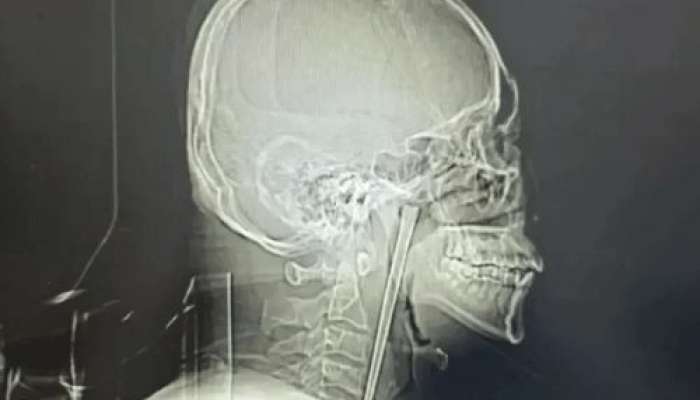

Həkimlər